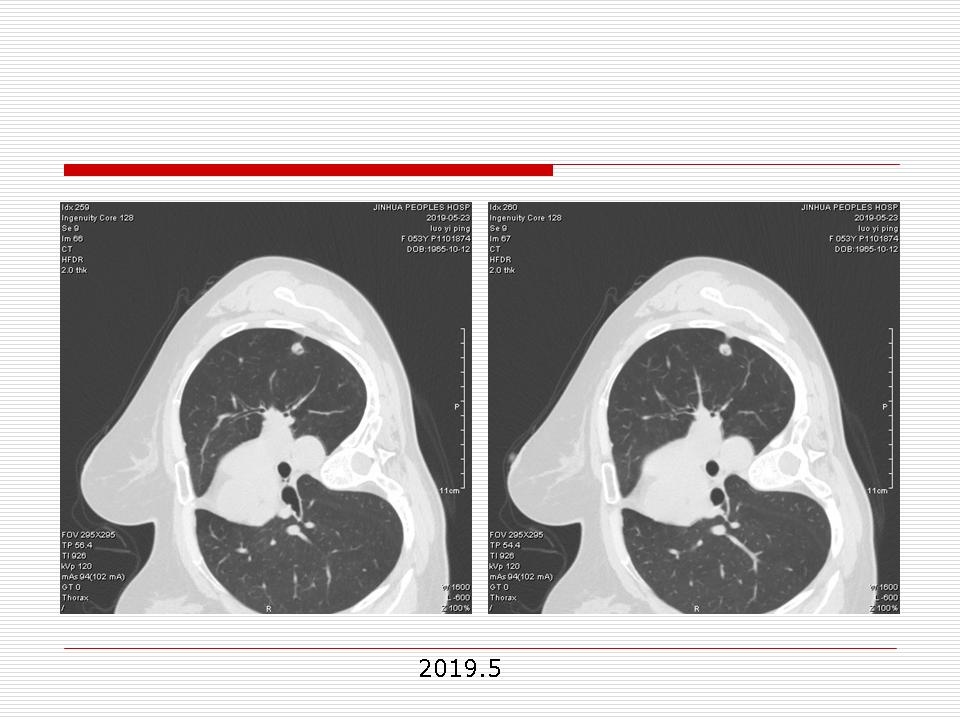

肺部阴影永恒且最重需要鉴别的是:到底是炎症还是肿瘤?但临床的病例中的影像表现难以界定或有些肿瘤特征,同时又有些炎症特点是非常常见的情况。作为临床医生我们怎么去总结分析,并找到之所以是炎症或之所以是肿瘤的细微差别或特点非常重要,也非常有用。2019.12.7浙江省2019年胸心外科学学术年会在宁波召开时,我的临床病例分析与经验总结<那些像肺癌的炎症与像炎症的肺癌>获得在大会交流的机会,以下为该PPT的内容,与你分享,希望对同道有益,有借鉴与启迪。若有探讨与进一不完善的建议,欢迎文末留言讨论: